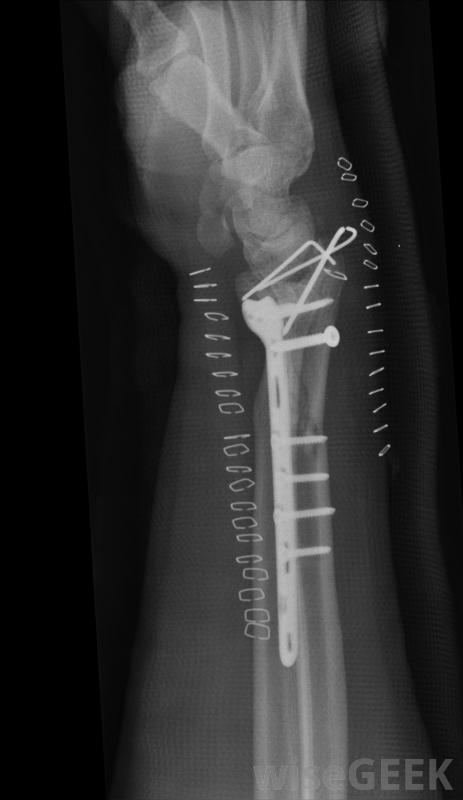

嚴重的撞擊骨折通常需要使用鋼板,用桿和螺釘將骨重新對齊。

當阻生骨折涉及大量骨碎片時,可能需要手術嚴重粉碎的骨頭通常需要重建以避免進一步的損傷和正確的愈合。外科植入物,如金屬螺絲釘、金屬棒或金屬針也可能被用來保持骨頭的正確連接。手術后,受影響的區域可能需要一段時間的石膏或吊索,以限制活動,并使碎片重新團聚。

術后,受影響區域可能需要一段時間的石膏或吊索,以使骨碎片重新團聚。